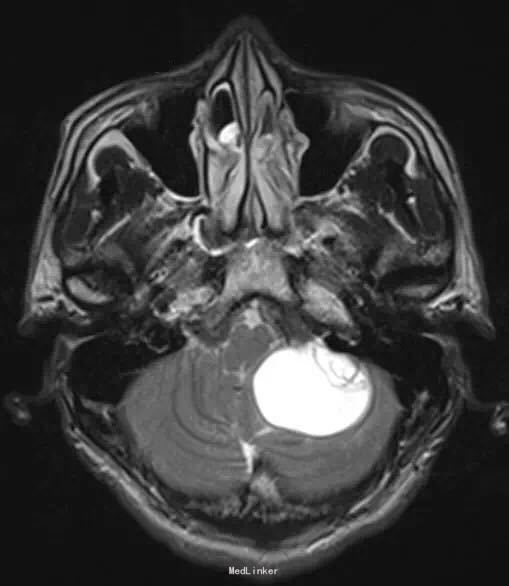

26 岁男性,头疼,恶心,出现加重性嗜睡一个月。

脑 MRI 检查示,左小脑半球一囊性成分为主的病灶,边界清楚,增强扫描见明显强化壁结节。可有轻度血管源性水肿和轻微局部占位效应,临近的四叠体和中脑周围池受压。GRE 序列上未见相关性出血的征象

诊断:小脑血管母细胞瘤。 整块切除 + 术前栓塞术。 可辅助立体定向放射外科技术。